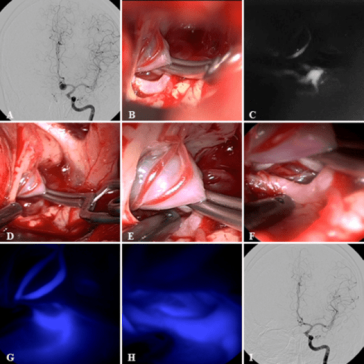

Revolutionizing Craniocervical Dural Imaging with Endoscope Integrated Indocyanine Green Videoangiography

Understanding the Challenges of Craniocervical Vascular Malformations In recent years, the management of vascular malformations at the craniocervical junction has been on the forefront of neurosurgical innovation. This editorial takes a closer look at the evolving techniques that combine advanced imaging technology with minimally invasive procedures, focusing on the role of endoscope‐integrated indocyanine green (ICG) […] More